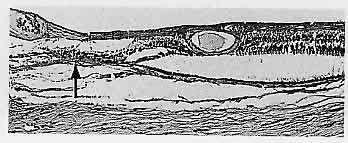

study. Arch Ophthalmol 108:1094, 1990 145. Massicotte SJ, Folberg R, Torczynski E et al: Vitreoretinal traction and perimacular retinal folds in the eyes of deliberately

traumatized children. Ophthalmology 98:1124, 1991 146. Maumenee IH: Vitreoretinal degeneration as a sign of generalized connective tissue diseases. Am J Ophthalmol 88:432, 1979 147. Nasr YG, Cherfan GM, Michels RG, Wilkinson CP: Goldmann-Favre Maculopathy. Retina 10:178, 1990 148. Brockhurst RJ, Albert DM, Zakov ZN: Pathologic findings in familial exudative vitreoretinopathy. Arch Ophthalmol 99:2143, 1981 149. Boldrey EE, Egbert P, Gass JDM, Friberg T: The histopathology of familial exudative vitreoretinopathy: A report of